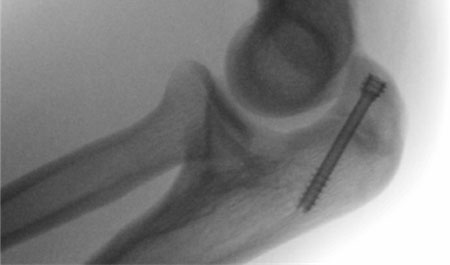

- Surgical treatment typically consists of partially threaded compression screws placed perpendicular to the facture line along the longitudinal axis of the ulna

- ROM initiated within 1-2 weeks with progression to full ROM as tolerated

- Non-weight bearing precautions and limiting resisted elbow extension until fracture is healed

- Interval throwing can begin once fracture is healed (typically between 8-12 weeks) and return to sport at 3-6 months